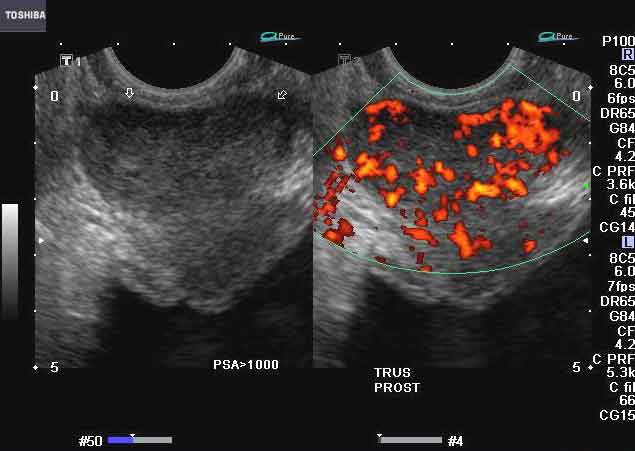

carcinoma-prostata

Per i pazienti affetti da cancro alla prostata e’ importante conoscere nel dettaglio come e quando uno dei vari trattamenti disponibili puo’ provocare effetti collaterali poco piacevoli e in particolare incontinenza urinaria e funzionalita’ sessuale. carcinoma-prostataUn gruppo di ricercatori del Fox Chase Cancer Center ha presentato alla riunione della Societa’ americana di radioterapia onologica i risultati di uno studio condotto su un campione di 17mila pazienti che cerca di chiarire proprio questi aspetti.